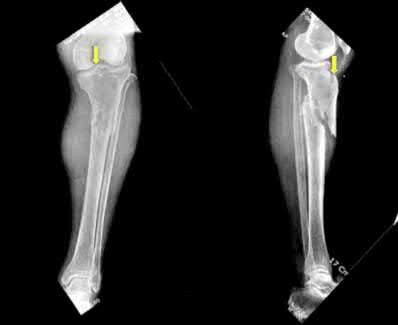

Question 9:

A 15-year-old male presents with deep knee pain. Radiographs reveal a mixed lytic and sclerotic lesion in the distal femur metaphysis with a "sunburst" periosteal reaction. Biopsy confirms high-grade conventional osteosarcoma. What is the most appropriate next step in management?

Options:

- Wide surgical resection followed by radiation

- Neoadjuvant chemotherapy followed by wide surgical resection and adjuvant chemotherapy

- Primary amputation

- Curettage and bone grafting

- Radiation therapy alone

Correct Answer: Neoadjuvant chemotherapy followed by wide surgical resection and adjuvant chemotherapy

Explanation:

The standard of care for high-grade conventional osteosarcoma is neoadjuvant (preoperative) chemotherapy, followed by wide surgical resection (limb-sparing surgery if feasible), and then adjuvant (postoperative) chemotherapy.